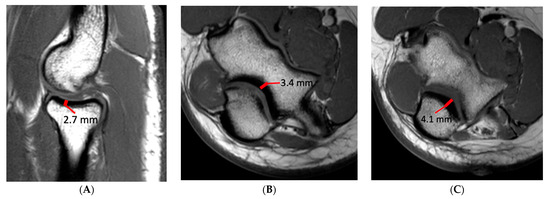

Injury of the UCL was scored as grade 1, 2 or 3. Injury was considered grade 1 if the ligament fibers were intact but there was periligamentous edema. If there was partial tearing of ligament fibers or abnormal signal within the UCL it was considered grade 2, and if fibers were completely disrupted it was considered grade 3. Ulnar collateral ligament (UCL) thickness and the maximal thickness of subchondral sclerosis in the central radial head, olecranon process, and posterior humeral trochlea were measured independently on separate workstations. UCL thickness was measured at the midpoint of the ligament on coronal fat-saturated T2-weighted or short-tau inversion recovery (STIR) images with a transverse measurement spanning the low signal ligament fibers and excluding any adjacent fat and fluid signal (Figure 1). The thickness of subchondral sclerosis in the radial head was measured on nonfat-saturated sagittal T1-weighted images, making the measurement perpendicular to the articular surface (Figure 2). On MR arthrograms the thickness of subchondral sclerosis in the radial head was measured on coronal non-fat-saturated T1-weighted images, as the only sagittal images acquired were fat-saturated. Subchondral sclerosis along the posterior humeral trochlea and olecranon process was measured on non-fat-saturated axial T1-weighted or proton-density-weighted images at the greatest anteroposterior length (Figure 2). No axial non-fat-saturated images were available in the MR arthrogram studies, but with appropriate windowing the subchondral sclerosis could still be readily identified on the fat-saturated images and was measured on the axial fat-saturated proton-density-weighted images.

Figure 2.

A 16-year-old male baseball pitcher with images demonstrating the measurement technique for quantifying subchondral sclerosis (thick red line). (A) Sagittal T1-weighted image demonstrating the measurement technique at the radial head, taken parallel to the articular surface; (B) axial T1-weighted image demonstrating the measurement technique at the posterior humeral trochlea, again made parallel to the articular surface; (C) axial T1-weighted image demonstrating the measurement technique at the olecranon process.